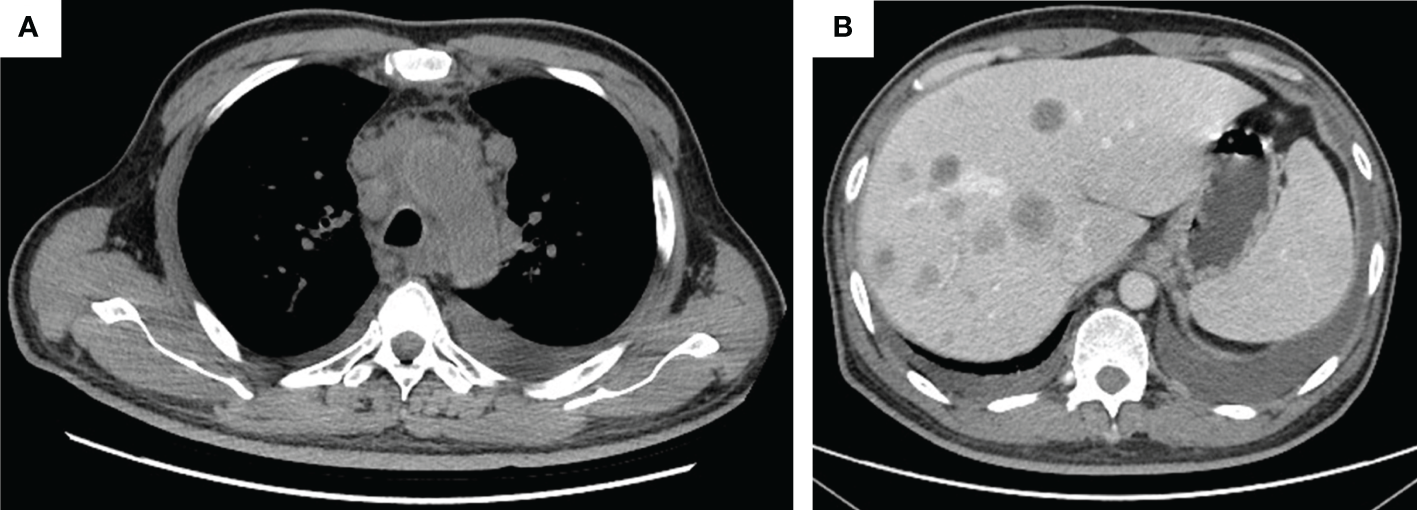

Figure 2

Thorax CT imaging indicates pulmonary inflammation after treatment of tislelizumab plus albumin-bound paclitaxel, which disappears in approximately 2 months when monitored closely. (A) Imaging on 16 July 2020, after two cycles immunotherapy, inflammation focally affecting the left lung; (B) imaging on 22 July 2020, 1 week after the time of (A), the inflammation is still in the left lung; (C) imaging on 9 September 2020, after three cycles immunotherapy, the inflammation basically subsided.

The patient was admitted in our hospital for cough, tight chest, and dyspnea on 15 March 2021. CT imaging demonstrated enlarged lesions in the mediastinum and multiple live metastases (Figures 3A, B). In consideration of the poor physical condition, the patient was treated with optimal supportive care. The patient died in October 2021. The treatment timeline is summarized in Figure 4. The biochemical analysis results of CEA, neuron-specific enolase (NSE), cytokeratin 19 fragments (CYFRA21-1), and albumin were collected. The change in cytokeratin is summarized in Supplementary Figure 1.

Figure 3

The tumor progression by thorax and abdomen CT imaging. (A) Thorax imaging indicates enlarged lesions in the mediastinum on 16 March 2021; (B) abdomen imaging on 16 March 2021 indicates multiple live metastases.